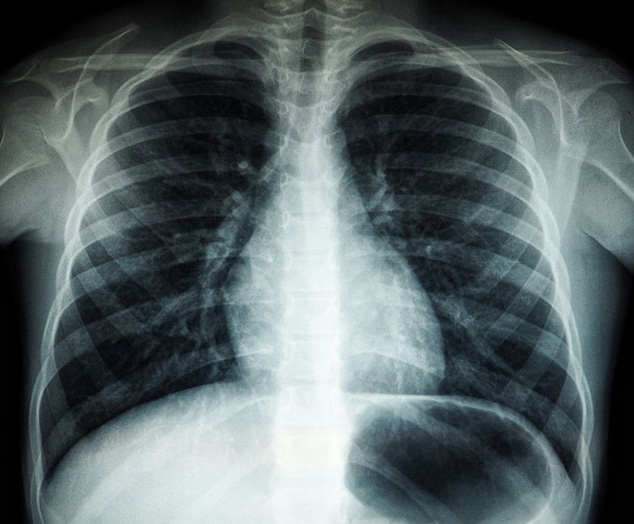

Pulmonary fibrosis (PF) is a progressive, interstitial lung disease characterized by scarring of the lung parenchyma that leads to irreversible loss of lung function. It is defined histopathologically by fibroblast proliferation, extracellular matrix deposition, and architectural distortion, with idiopathic pulmonary fibrosis (IPF) representing the most common and severe form. The disease arises from repeated alveolar epithelial injury, abnormal wound healing responses, fibroblast activation, and dysregulated immune signaling, leading to thickened, stiffened lungs with impaired gas exchange. Clinically, PF presents with dyspnea, chronic cough, reduced exercise tolerance, and low diffusion capacity. Progressive disease results in respiratory failure, pulmonary hypertension, and premature death, with median survival for IPF patients only 3–5 years after diagnosis.